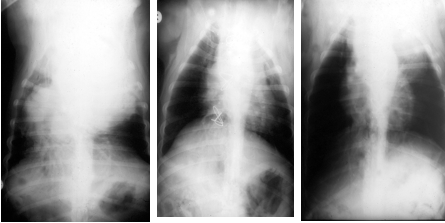

What can be seen in these images?

Dog that had thoracic surgery, has radio dense mass in throax which was displacing heart – chest opened up (middle pic) and heart put back in right place. Mass ended up being a large haemangiosarcoma – 6 months later, it reoccurred